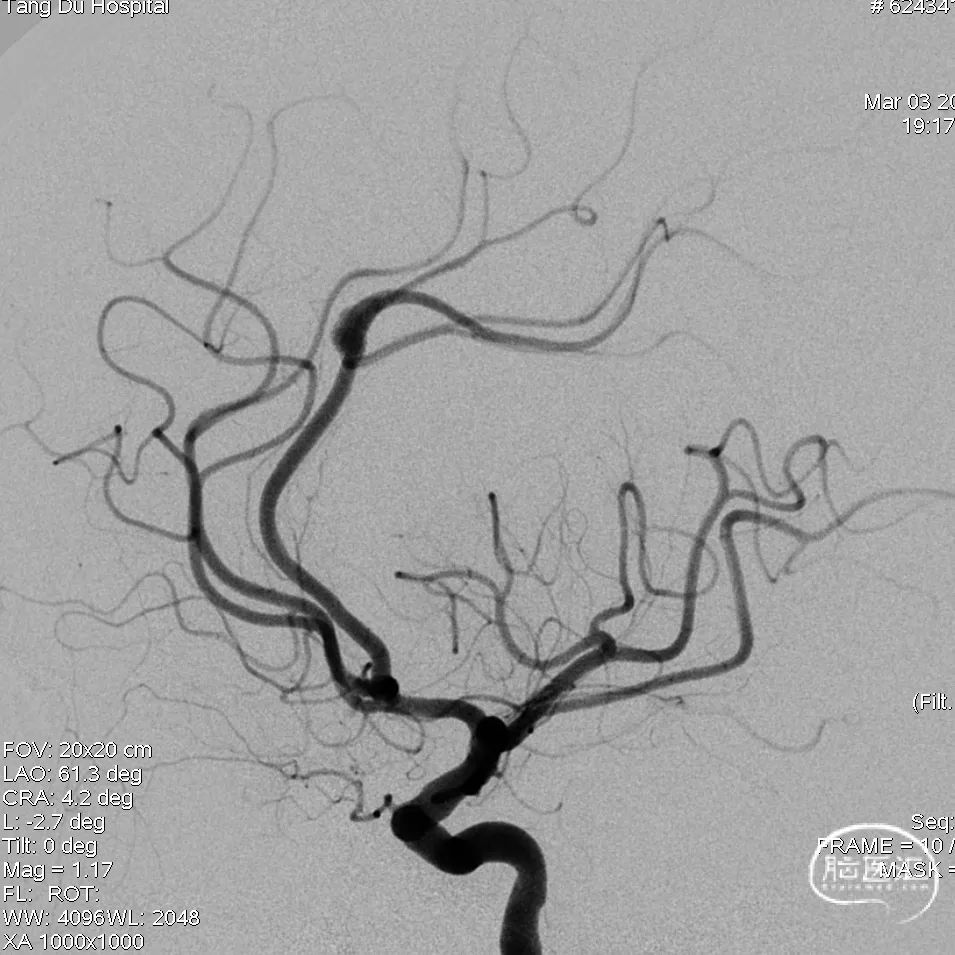

术后正侧位造影显示支架贴壁良好,血管重塑满意,血流改善明显。

将血流导向密网支架经微导管同轴通过动脉瘤,缓慢撤微导管释放血流导向密网支架,全程放完后,再次造影确定支架内血流通畅。

再次行全脑血管造影,见血流灌注良好、通畅,退出导管。